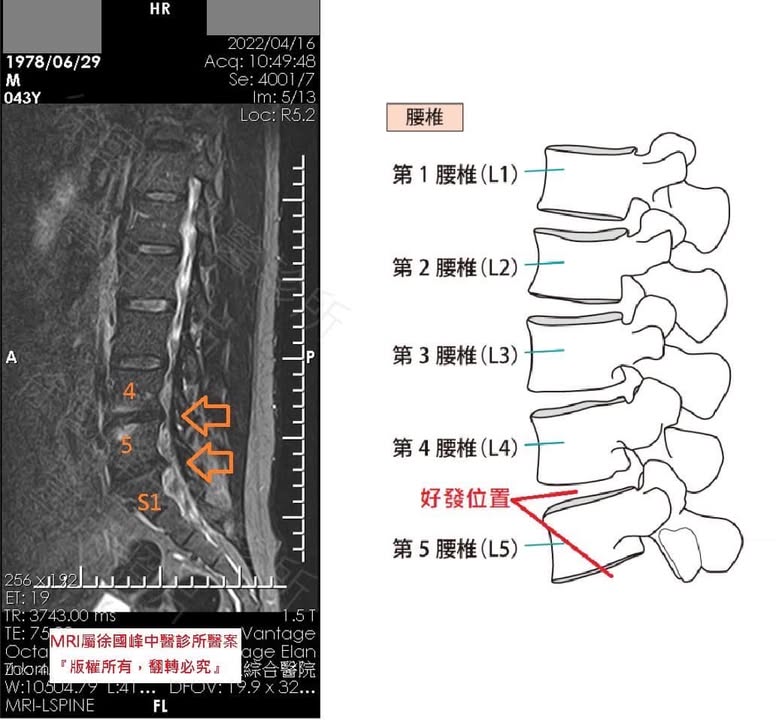

1.左側L4L5;L5S1 中重度椎間盤突出